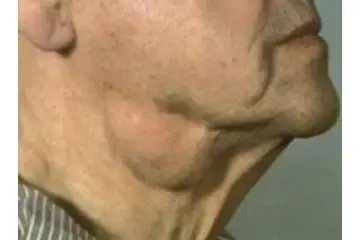

Omuzda yağ bezesi, tıpta lipom olarak adlandırılan, genellikle zararsız ve yavaş büyüyen yağ dokusu kütleleridir. Bu bezeler, vücudun herhangi bir yerinde, özellikle de omuz ve sırt bölgelerinde, ortaya çıkabilir. Genellikle yumuşak, hareketli ve ağrısızdırlar. Ancak, bazı durumlarda, bu bezelerin belirtileri ve tedavi yöntemleri hakkında bilgi sahibi olmak önemlidir. Yağ Bezesi Nedir?Yağ bezeleri, yağ hücrelerinin anormal bir şekilde birikmesi sonucu oluşan şişliklerdir. Bu kütleler genellikle derinin altında, kasların üzerinde veya iç organların çevresinde gelişebilir. Lipomlar genellikle iyi huyludur ve kanser riski taşımazlar. Belirtileri Omuzda yağ bezesi belirtileri şunlar olabilir:

Tedavi Yöntemleri Çoğu durumda, omuzda yağ bezesi tedavi gerektirmez; çünkü bu kütleler genellikle zararsızdır. Ancak, estetik kaygılar veya rahatsızlık hissi durumunda tedavi seçenekleri mevcuttur: